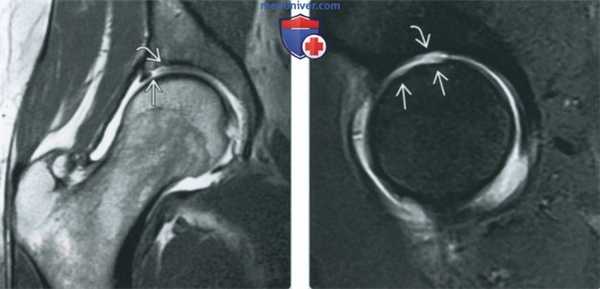

(Слева) МР-артрография в режиме Т1ВИ FS, косоаксиальный срез, пациент с жалобами на рецидив боли после артроскопической коррекции разрыва суставной губы и резекции костного выступа: определяется, что восстановленный участок суставной губы имеет выражено неравномерный контур, однако является интактным, о чем свидетельствует отсутствие затека контраста в суставную губу. Для выявления рецидивирующего разрыва суставной губы лучше выполнить МР-артрографию в режиме Т1ВИ.

(Справа) МР-артрография в режиме Т1ВИ FS, косоаксиальный срез, этот же пациент: выявляется отслоение суставной губы ниже восстановленного участка. Область, подвергшаяся остеохондропластике, ничем не примечательна. (Слева) МР-артрография в режиме Т2ВИ FS, коронарный срез, этот же пациент: суставная капсула растянута, восстановленный участок суставной губы имеет неровный контур и содержит зону, интенсивность сигнала которой соответствует интенсивности сигнала от жидкости. Для дифференциации грануляционной ткани и контрастного препарата в разрыве суставной губы, необходим режим Т1.

(Справа) МР-артрография в режиме PD FS, сагиттальный срез, этот же пациент: отмечается неровный контур восстановленного участка суставной губы, а также локальное истончение суставного хряща. Область, подвергшаяся остеохондропластике, ничем не примечательна.